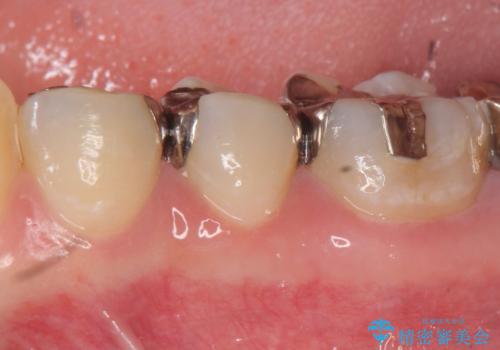

- 銀歯を装着してから時間が経っているので一度外して審美的な修復治療を受けたい、と希望され来院されました。

銀歯周囲の天然歯を削らないよう、拡大鏡下で丁寧に銀歯を除去したのちに審美性・精密性に優れるセラミックインレーを用いた修復治療を行っていきます。

- 23.1万円 セラミックインレー×3費用は治療当時の料金となります